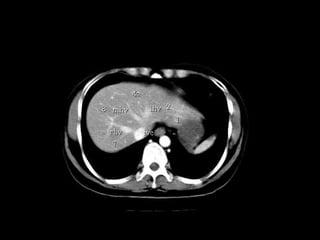

Radiographers use medical imaging equipment like X-rays and MRIs to produce images of patients' internal structures and organs. They are responsible for positioning patients, operating scanning machines, and ensuring quality images. Radiographers must have strong attention to detail, excellent communication skills, and the ability to work well under pressure to accurately capture anatomical features and diagnose any abnormalities.